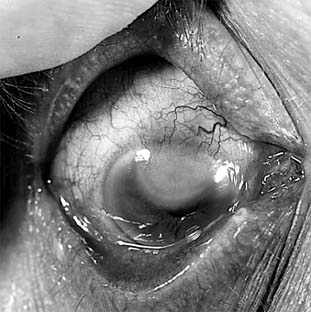

Attacks of the common recurrent type of herpetic keratitis (Figure 6-4) are triggered by fever, overexposure to ultraviolet light, trauma, psychic stress, the onset of menstruation, or some other local or systemic source of immunosuppression. Unilaterality is the rule, but bilateral lesions develop in 4-6% of cases and are seen most often in atopic patients.

Figure 6-4

Figure 6-4: Corneal scar caused by recurrent herpes simplex keratitis.